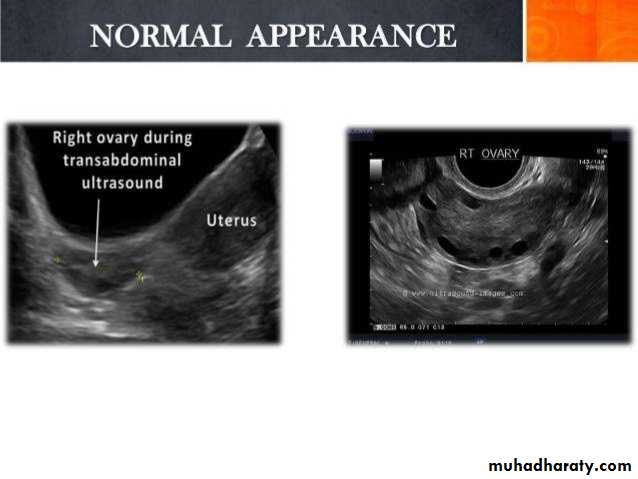

Ovarian cysts

Ovarian cysts are commonly encountered in gynecological imaging, and vary widely in etiology, from physiologic, to complex benign, to neoplastic.

Small cystic ovarian structures should be considered normal ovarian follicles unless the patient is pre-pubertal, post-menopausal, pregnant, or the mean diameter is >3.0 cm

Radiographic features

Ultrasound is usually the first imaging modality for assessment of ovarian lesions. Simple ovarian follicular cysts are:

anechoic

intraovarian or exophytic;

have an imperceptible wall